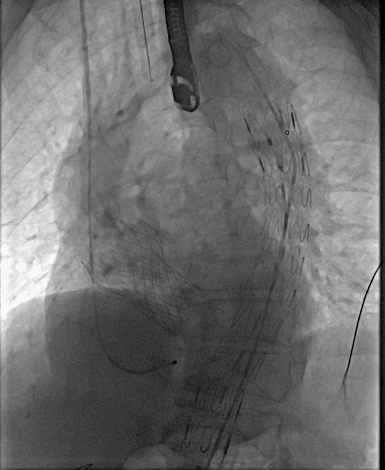

TAVR-VenusA-Plus植入后

手术演示中

经右侧股动脉途径送入LifeTech Ankura 28*160mmm大动脉覆膜支架,支架远端定位于腹腔干开口上缘,准确定位后释放大血管支架。

再行降主动脉造影见主动脉支架贴壁良好,透壁溃疡完全隔绝,未见明显内漏,腹腔干开口未受影响,血流通畅。

TEVAR-主动脉覆膜支架植入后